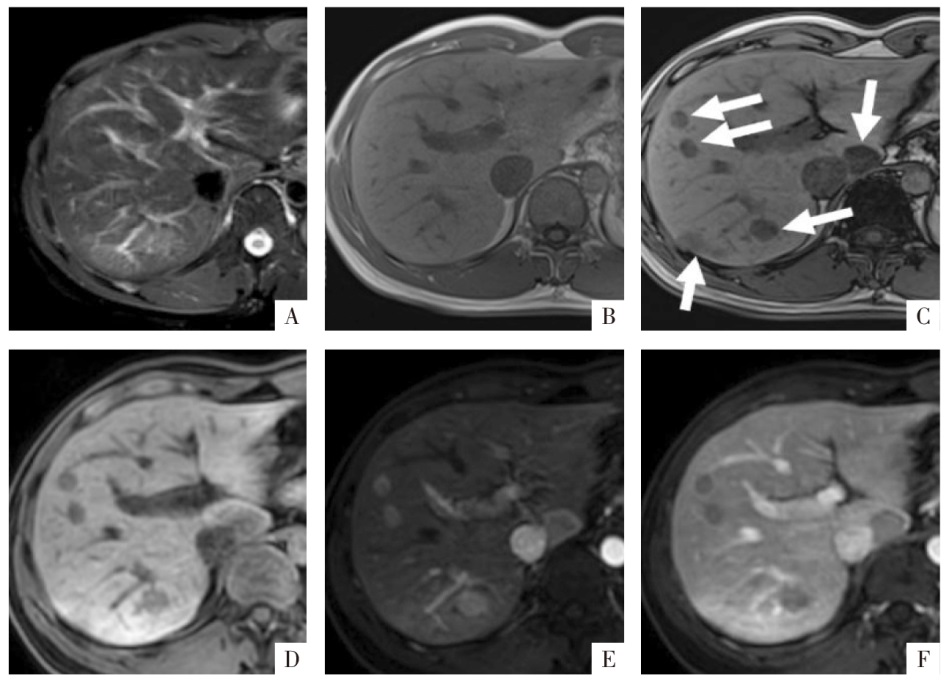

图11

病人男,25岁,查体发现肝肿块3年余,肿瘤标志物阴性。手术病理诊断为含局灶性重度脂肪变性的FNH。A图,T

2

WI上病变呈稍高信号肿块,B、C图为同反相位,病变内部同相位呈稍高信号,反相位表现勾边效应,类似“小脂肪块”(箭头);D—G图分别为蒙片、动脉期、门静脉期及延迟期影像,病灶呈动脉期略不均匀高强化,但无廓清。